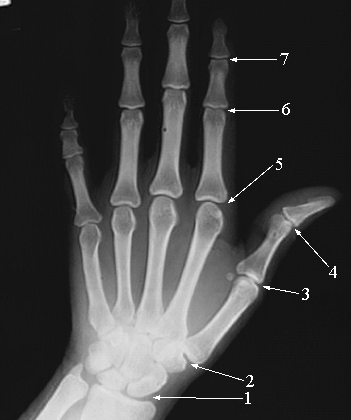

- Joint Between Radius and Navicular (Scaphoid) bones (Radiocarpal Joint)

- Joint Between Trapezium and First Metcarpal Bones (carpometacarpal Joint)

- First Metacarpophalangeal Joint

- Interphalangeal Joint of the Thumb

- Second metacarpo-phallangeal joint

- Proximal inter-phallangeal joint

- Distal inter-phallangeal joint.